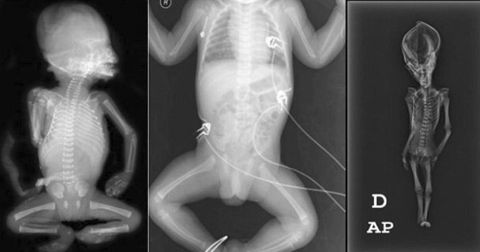

Uzaylı mumyası olduğu iddia edilmiş! Tüm sır çözüldü

Galerinin tamamı için tıklayınızCalifornia Üniversitesi, San Francisco Üniversitesi ve Stanford Üniversitesi tarafından “Ata” ismi verilen mumyaya yapılan DNA analizleri, ,gizemini uzun süre koruyan kalıntının, çeşitli genetik mutasyonlara uğramış, 6-8 yaşında olduğu tahmin tahmin edilen cüce bir kız çocuğuna ait olduğunu ortaya koymuştu. Yapılan bilimsel çalışmalar, çocuğun 40 yıl önce öldüğünü ve bugüne kadar tanımlanmamış olan gen bozukluklarına sahip olduğunu açığa çıkarmıştı.